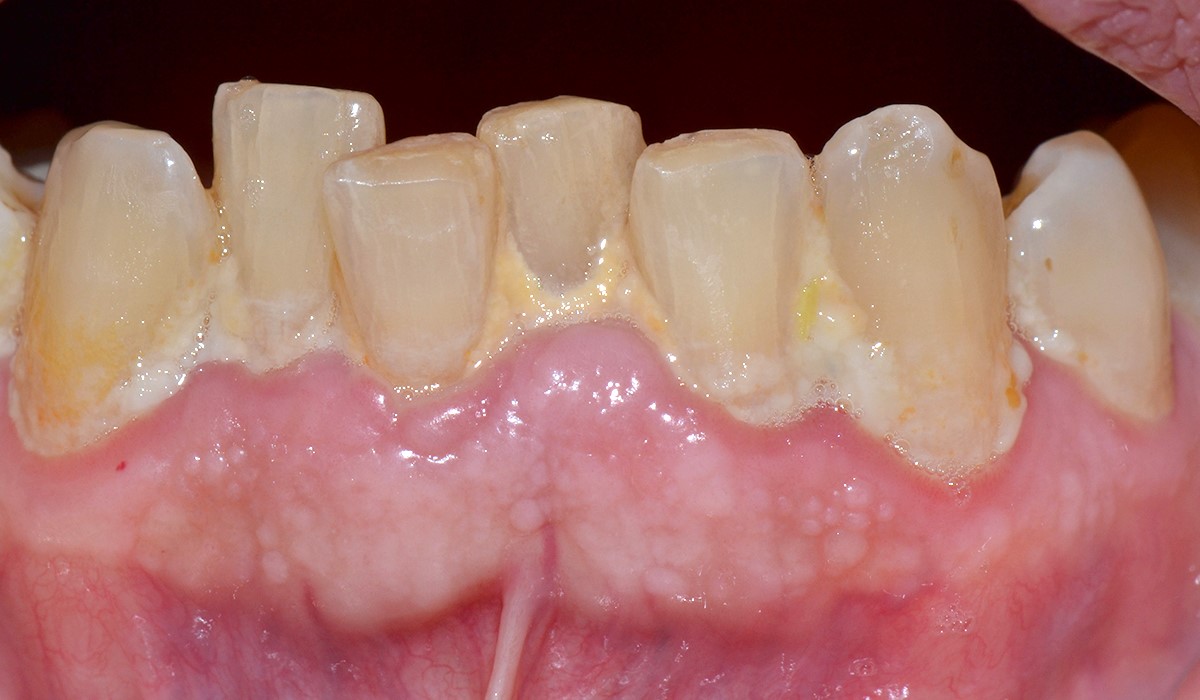

Patient avec des chevauchements dentaires favorisant l’apparition de tartre. Des facettes céramique sont réalisées de manière à rétablir une implantation correcte des incisives inférieures.